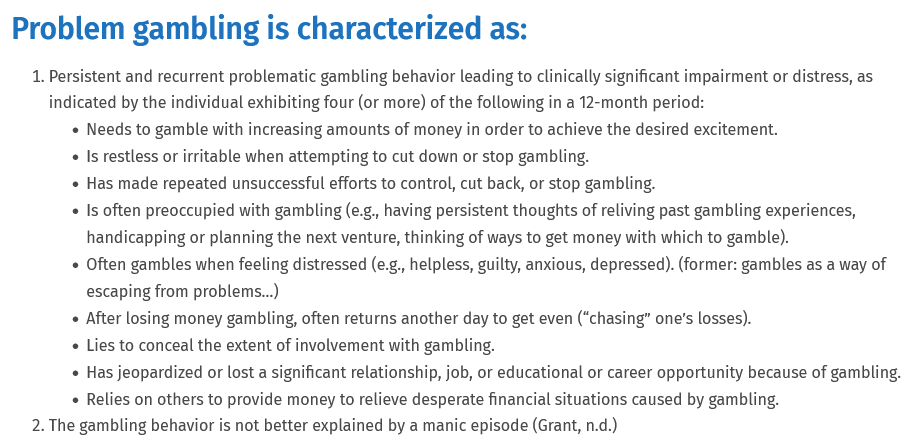

Signs of a Gambling Addiction

- Frequent thoughts about gambling.

- Has it Ever Caused “YOU” to have Difficulty Sleeping?

- Need to gamble with increasing amounts to achieve the desired excitement.

- Repeated unsuccessful efforts to control, cut back on or stop gambling.

- Restlessness or irritability when trying to cut down or stop gambling.

- Gambling when trying to escape from problems or negative mood or stress.

- After losing an item of value by gambling, feeling the need to continue to get even.

- Often gambling when feeling distressed.

- After losing money gambling, often returning to get even.

- Lying to hide the extent of gambling involvement.

- Have You Ever Felt Remorse after Gambling?

- Losing important opportunities such as a job or school achievements or close relationships due to gambling.

- Relying on others to help with money problems caused by gambling.

- Have You Ever Gambled Down to Your Last Dollar?

- Have You Ever Considered Harming “Yourself” as a Result of Your Gambling?